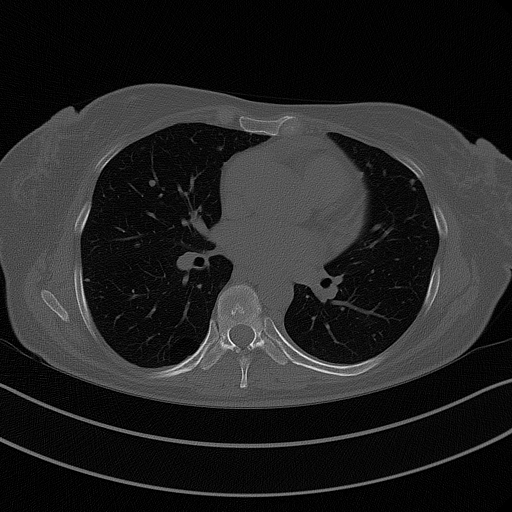

Image Grid

4×3 grid: Rows show different image types (Original NATIVE, Reconstructed NATIVE, Original VENOUS, Generated VENOUS), Columns show windowing techniques (No Window, Lung Window, Mediastinum Window)

Original NATIVE CT scan (input)

No window - Raw intensity values

Original NATIVE CT scan (input)

Lung window (WL -600, WW 1500 → Low −1350, High +150)